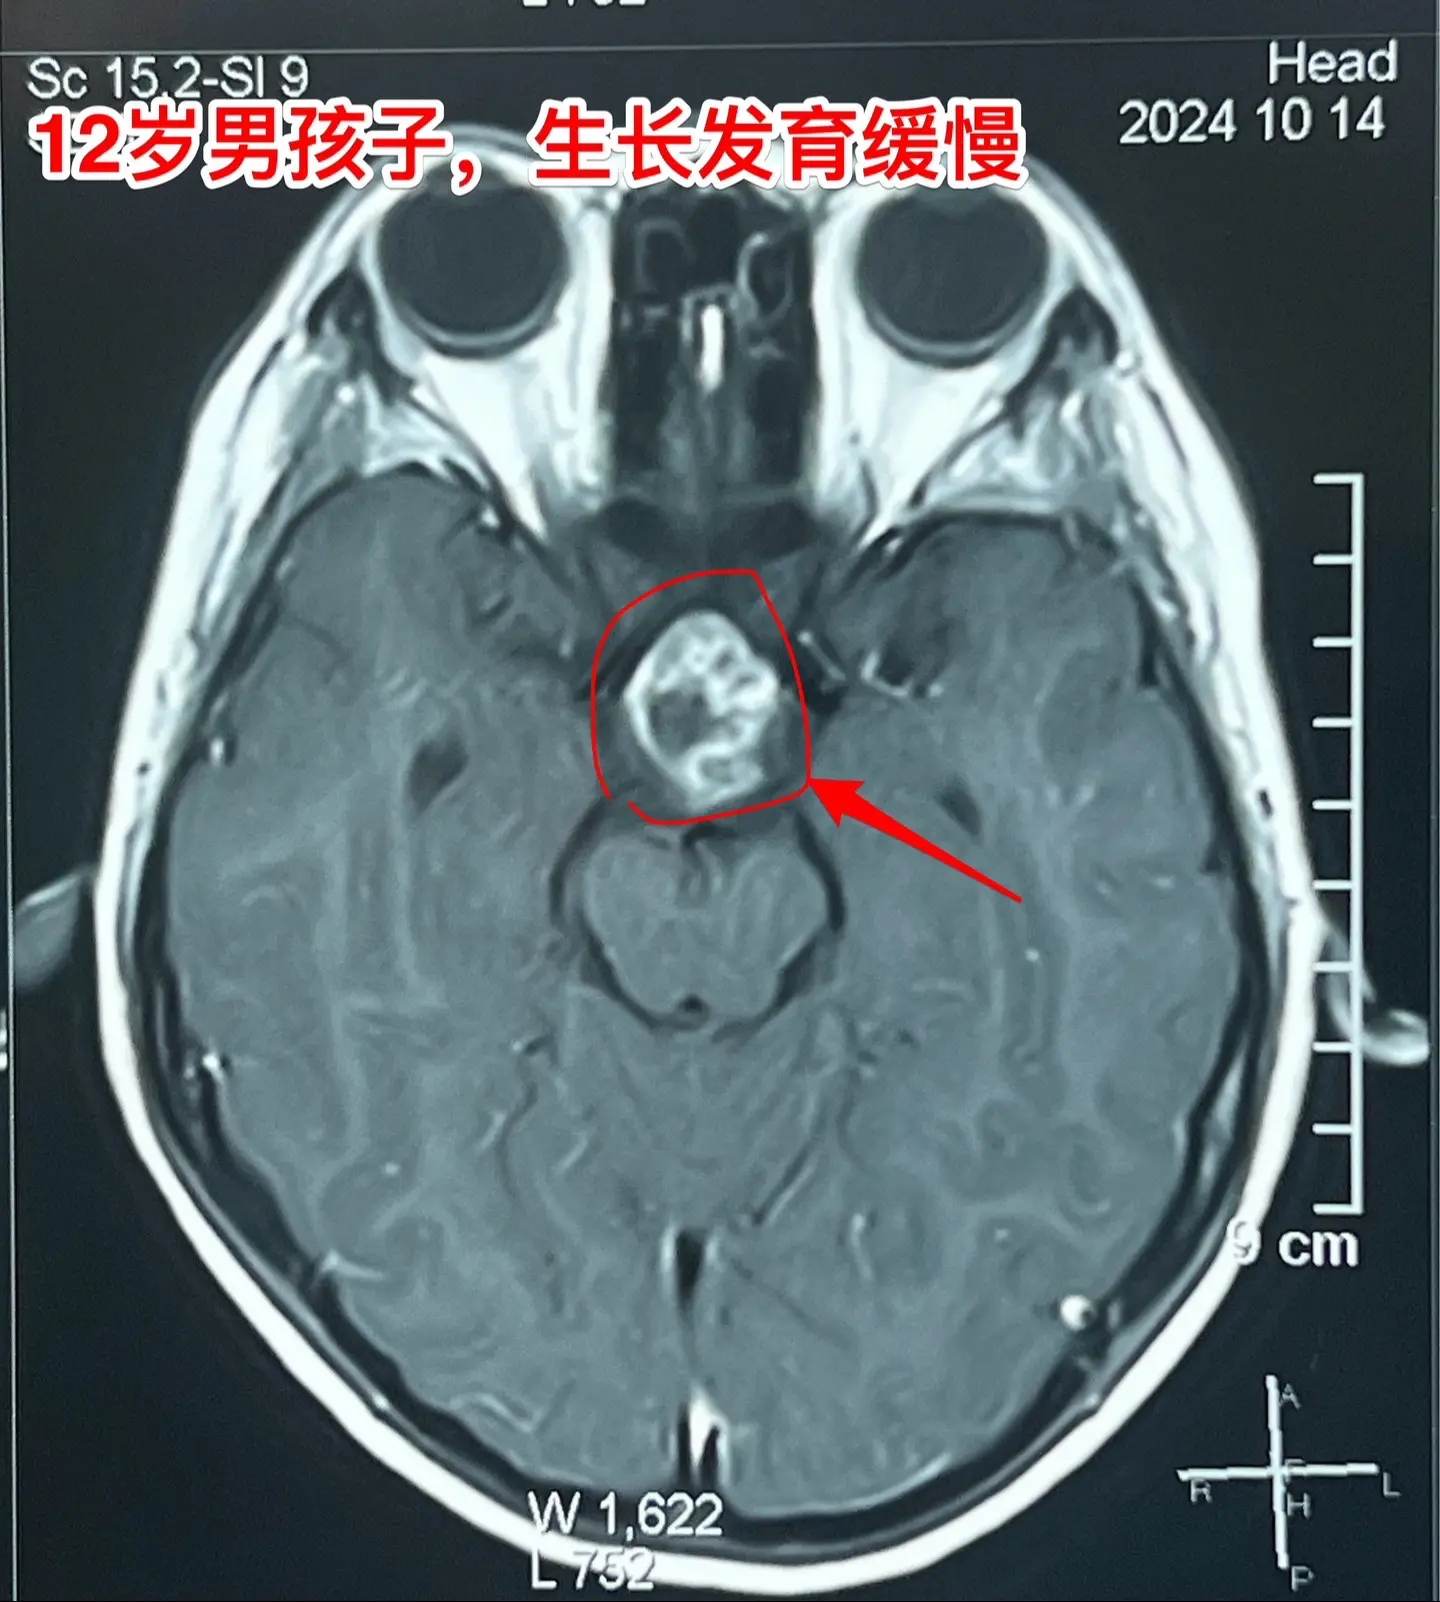

孩子生长发育缓慢,家长要重视。这个12岁的男孩子,在深圳生活,平时爱运动,除了生长发育缓慢之外似乎很“健康”。视力无下降,无头痛症状。 父母观察到孩子的生长发育问题,到医院去检查,发现脑部长了肿瘤,是典型的颅咽管瘤,有钙化。 这个颅咽管瘤是沿着垂体柄内部上下方向生长的,向上长进了第三脑室。这样的颅咽管瘤完全切除的难度比较大,垂体柄也难以保留。 2024.11.15顺利切除肿瘤。手术后患者患者很快就清醒了,从ICU转回来普通病房。希望肿瘤不复发。